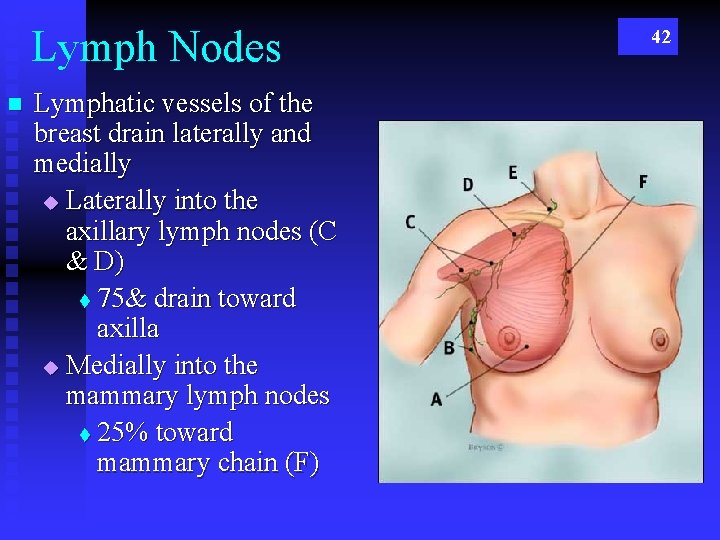

Lymph Nodes n Lymphatic vessels of the breast drain laterally and medially u Laterally into the axillary lymph nodes (C & D) t 75& drain toward axilla u Medially into the mammary lymph nodes t 25% toward mammary chain (F) 42